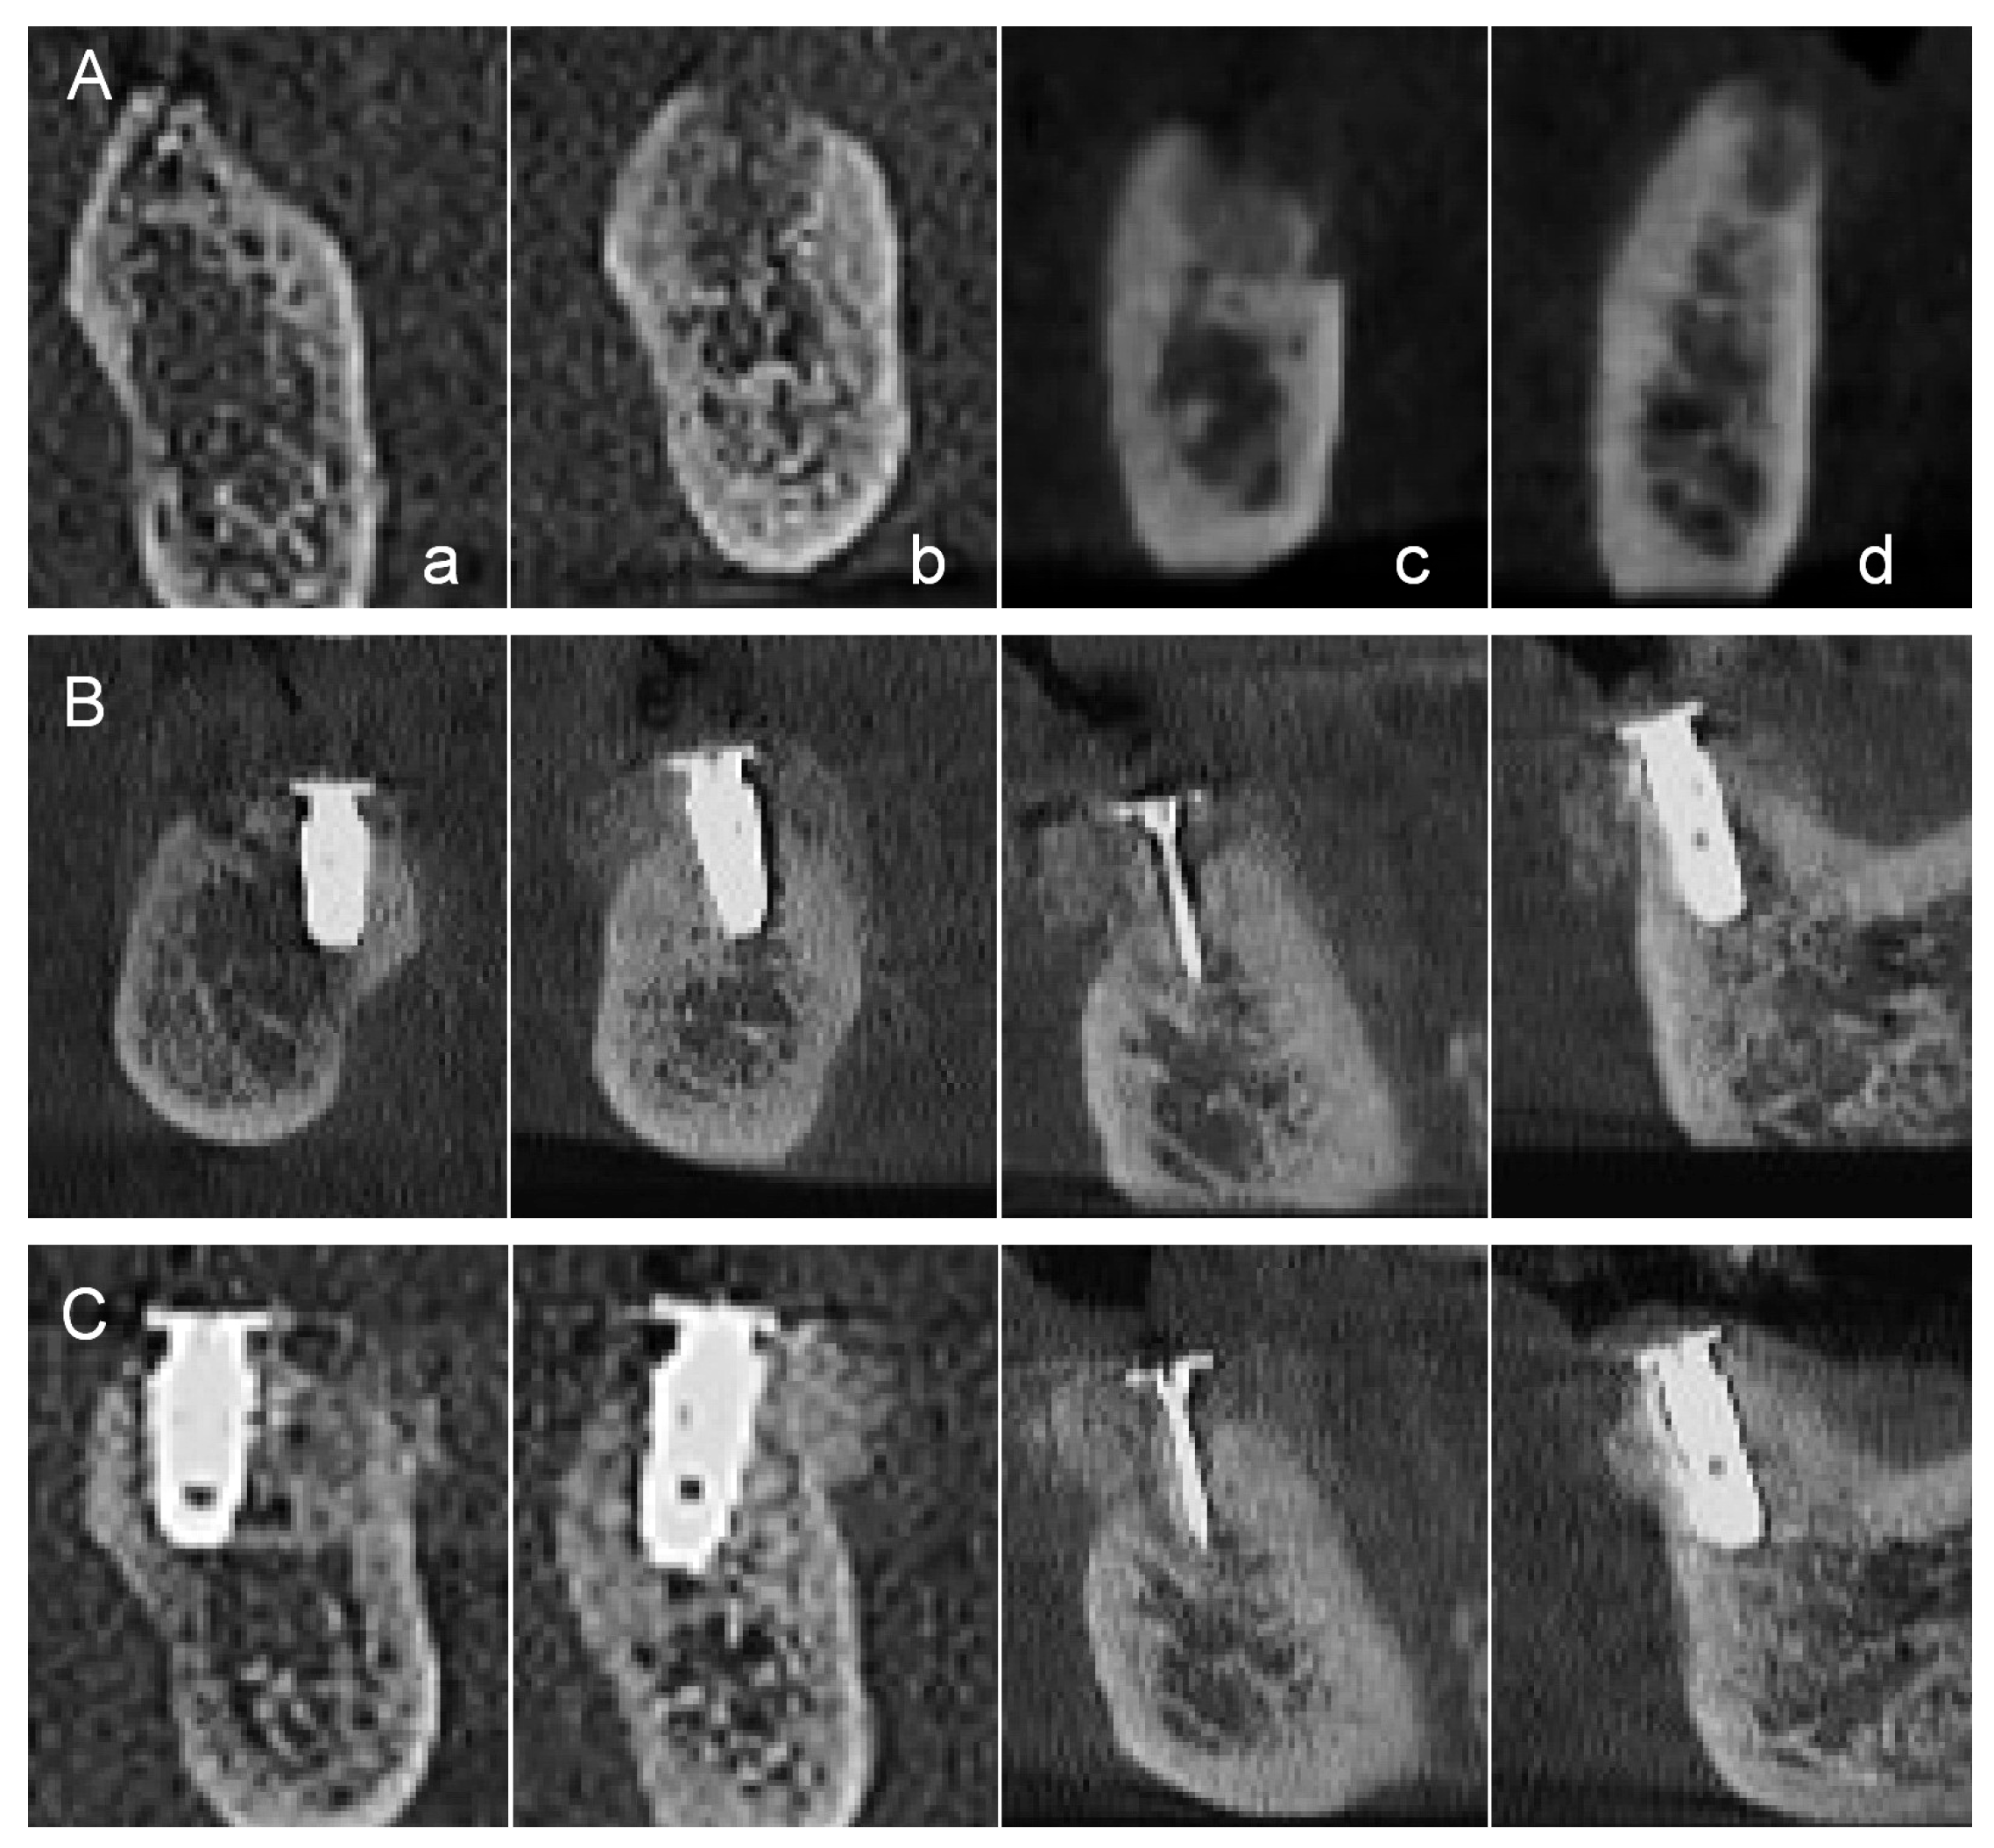

- Sohn, D.S. Reconstruction of three-dimensional alveolar ridge defects utilizing screws and implant abutments for the tent-pole grafting techniques. In Essential Techniques of Alveolar Bone Augmentation in Implant Dentistry, 2nd ed.; Tolstunov, L., Ed.; Wiley Blackwell: Hoboken, NJ, USA, 2023; pp. 404–418. [Google Scholar]

- Sohn, D.S.; Lui, A.; Choi, H. Utilization of tenting pole abutments for the reconstruction of severely resorbed alveolar bone: Technical considerations and case series reports. J. Clin. Med. 2024, 13, 1156. [Google Scholar] [CrossRef]